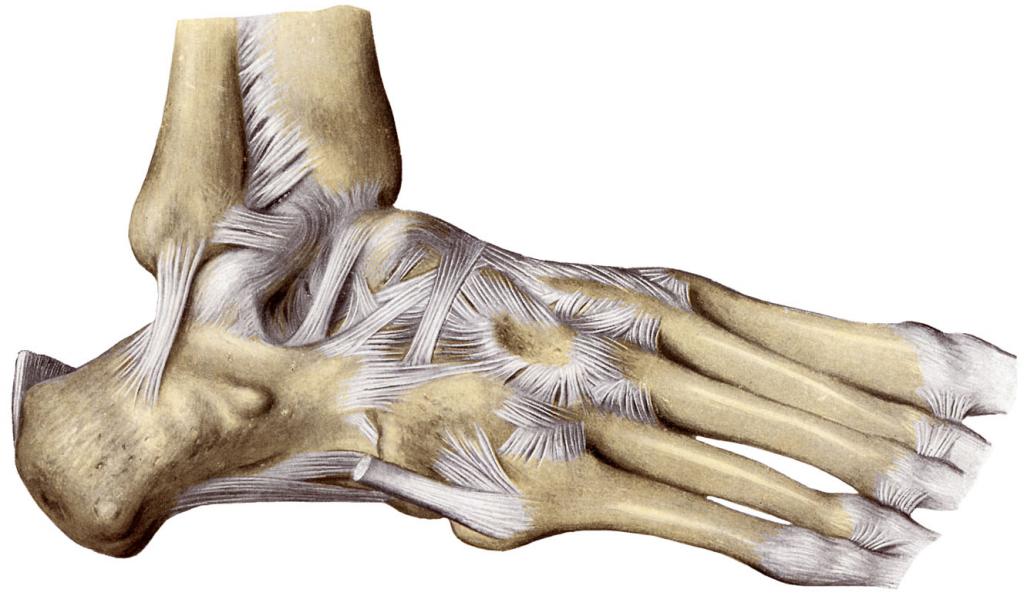

Анатомические особенности

Голеностопный сустав представляет собой важный элемент опорно-двигательного аппарата, который выдерживает вес человеческого тела. В этом суставе находятся следующие связки:

- Межберцовый синдесмоз.

- Нижняя задняя связка.

- Межкостная связка.

- Нижняя передняя межберцовая связка.

- Наружно-боковая связка.

- Дельтовидная связка.

Каждая из этих связок играет ключевую роль в обеспечении стабильности сустава. Поэтому даже при небольшом растяжении связки голеностопа могут возникнуть повреждения, что сопровождается характерными симптомами.